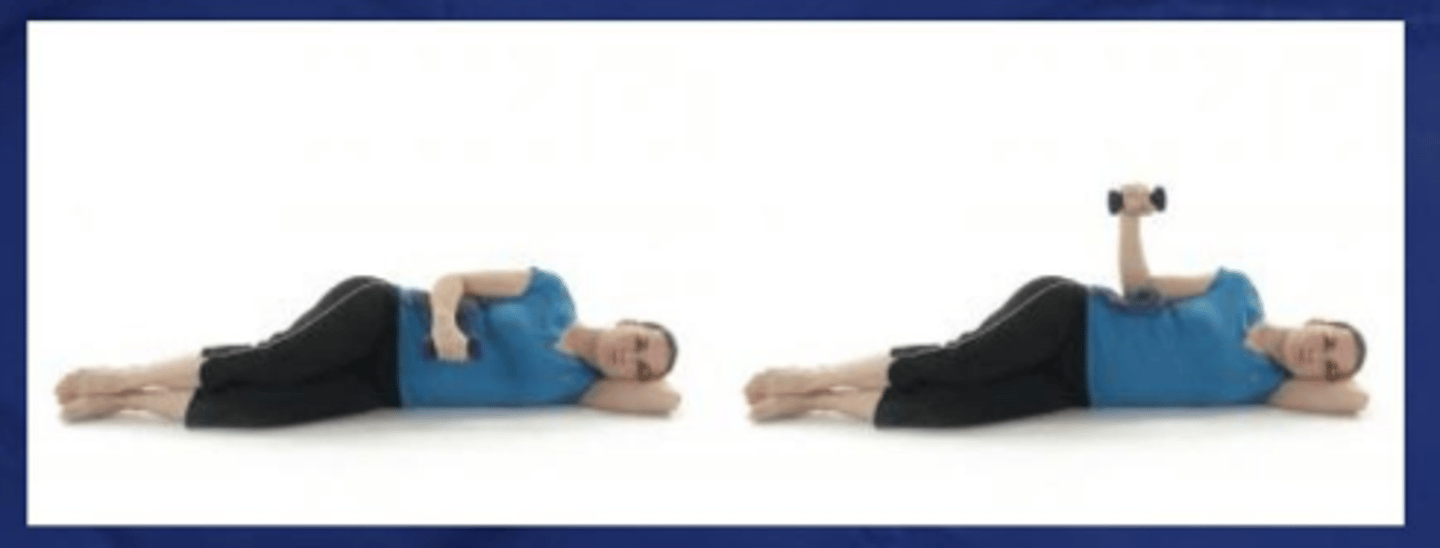

Sidelying ER

What does the image show?